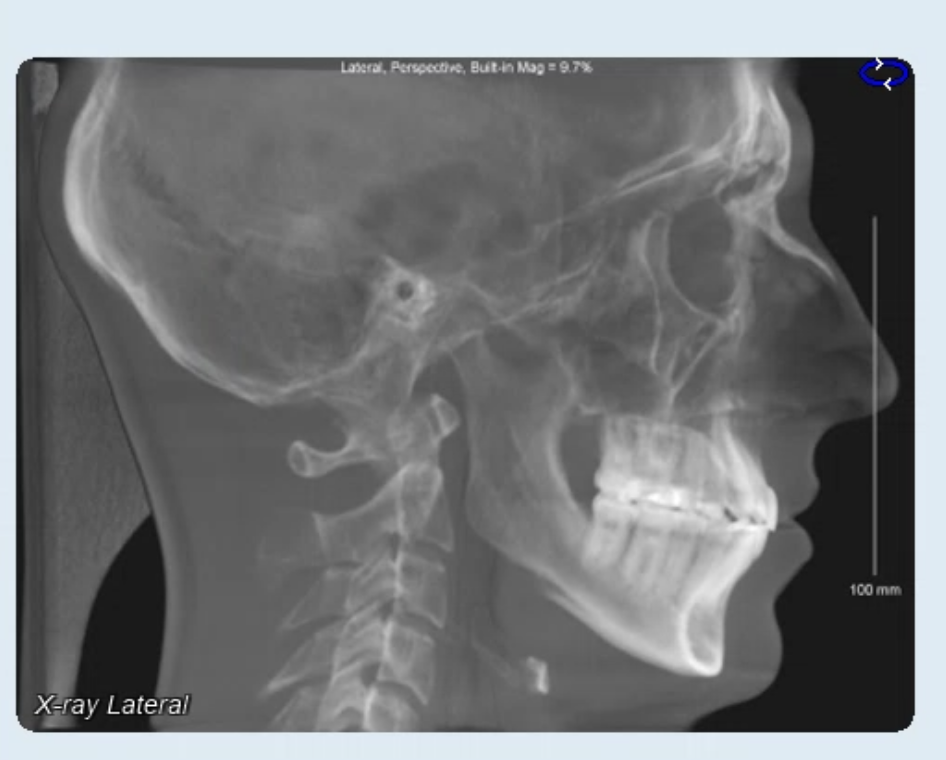

Am wondering if around 5mm genioplasty would be fine. Surgeon initially said 4mm with 1mm down, i asked for 5. Before ppl drop the jaw surgery talk, I know I probably do need that, but its not realistic for me to have that done right now, too expensive and dont have time for the recovery. I feel like I can get most of the aesthetic benefit from the genioplasty but lmk.

• Screenshot 2026-03-18 at 11.10.35 AM.png

Screenshot 2026-03-18 at 11.10.35 AM.png

415.5 KB · Views: 0